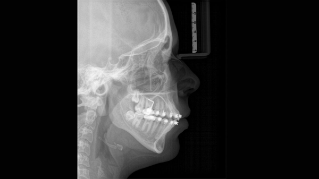

We developed a 10-point concept for easy patient positioning and X-ray imaging. Our concept is primarily about two things: high image quality and comfort for the patient and the assistant. This concept supports and provides the tools needed to ensure high-quality images for treatment analysis and focuses on ergonomics and comfort for the patient and assistant. The patented bite block technology, for example, automatically establishes the correct inclination of the patient's head, positioning the patient in the occlusal plane, partnering with the 3 point head fixation and firm handles to ensure stable positioning-limiting unnecessary correction scans.